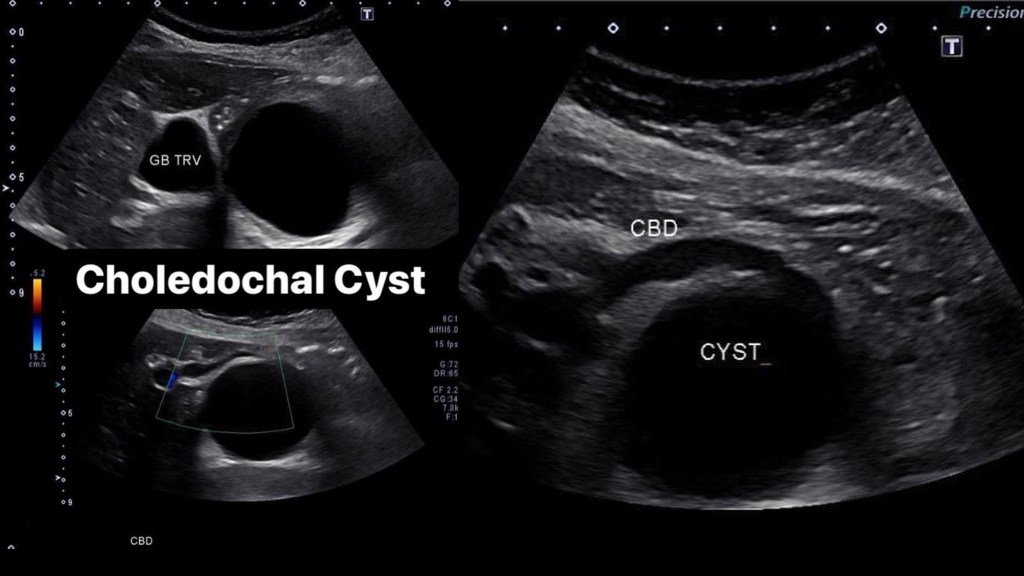

Choledochal cysts are routinely found on ultrasound in infancy, though they can be found on adults and fetal scans as shown below. An anechoic cyst will be present at or before the porta hepatis, size may be variable from small to quite large. In Caroli disease there will be innumerable intrahepatic cysts, this my be difficult to differentiate from polycystic kidney disease (ADPCKD) affecting the liver, typically ADPCKD cysts are non communicating. [3] Once found further imaging and work up must take place to properly classify and treat CC. Endoscopic Retrograde CholanigoPancreatography (ERCP) is the gold standard in diagnosing CC, however Magnetic Resonance CholangioPancreatography (MRCP) is now favored over ERCP due to its non-invasiveness and superior resolution. [5]

Case 1

Case 2